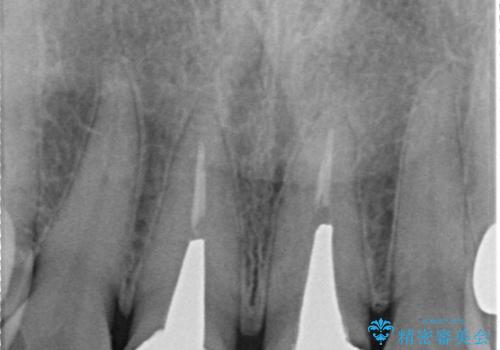

- 前歯の変色を主訴に来院されました。

根管治療、土台のやりかえも提案しましたが、金銭的理由より、クラウンのみの修復としています。

今後痛みが出た場合は、外科的歯内療法での対応を希望されています。